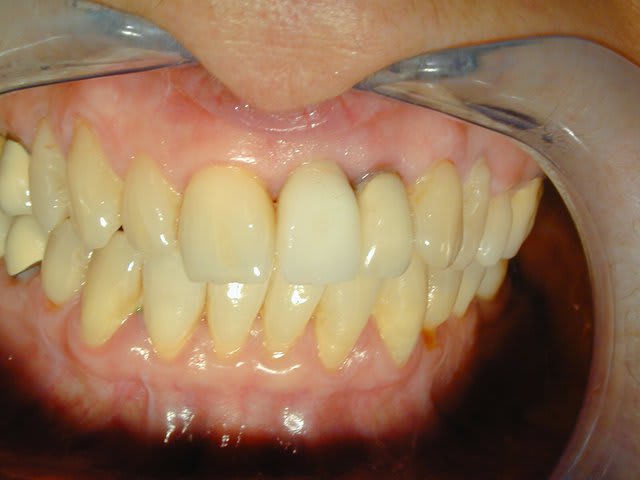

Voila: extraction curetage, implantation à 1 semaine, tranquille.

Le col de la prov est volontairement un peu étroit pour éventuellement faire un "Bichacho" plus tard.

Rom1 wmgjgx - Eugenol

Rom2 yakwup - Eugenol

Rom j14 hiy9ln - Eugenol

Longueur =16. Je n'avais pas de scan, mais j'avais la racine, elle fait 10, 3mm de granulome, il faut plus long si on aime les implants "minces" (ça c'est un autre débat)